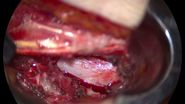

Here we go directly into the surgery. Here on the right side you have the temporal lobe, frontal lobe. Sometimes I use retractors but with very light pressure, no need to tell you too much about this. You see the MCA that comes around here, we expose the neck of the aneurysm, it’s not a big aneurysm, so we can almost fully expose it.

What you see here, as was shown before, you see this small temporal branch that was adherent to the aneurysm neck and needed to be prepared. So here preparation of this temporal branch, releasing it from the aneurysm so we can actually go beyond the aneurysm for our clipping.

[05:12]

Here you see the final preparation, it’s very important obviously to spare all the vessels, all of you know, no big discussion. We just enjoy some nice images. OK, so here is the clip application, I decided that I could do it with a single clip in the beginning, clip application and complete occlusion of the aneurysm without problem. So standard, after the clipping, is to use the micro-doppler to check for the vessel patency and check therefore for normal flow, that’s what I’m doing here. All these are standard procedures.

So now I go to the next generation. Here we see GLOW800. We have the same surgical field, so you imagine I’m still doing my procedure. I’m looking at the blood vessels and through my CaptiView, through the ocular that has an image injection, I will actually see the fluorescence of the blood vessels. With some patients, you will observe how the green contrast will arrive in the blood vessels. And now this is really the Augmented Reality because I can continue my surgical procedure and wait for the dye to come in, but I keep the full 3D overview of my surgical field.

I have the normal depth perception, the depth perception that I have normally with my microscope. I can zoom in and investigate if all the blood vessels are patent. And you see also the cortical surface with the green vessels and you see the aneurysm that has no more flow.